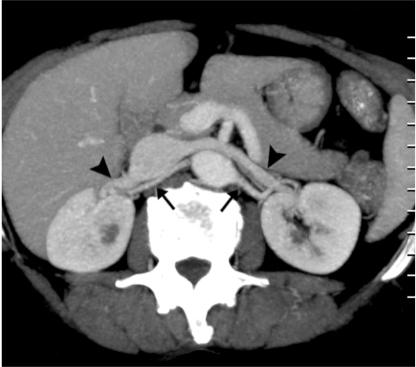

64 通道多排螺旋 CT 血管造影在评估肾血管解剖及可能变异中的应用:影像学研究。

The utility of 64 channel multidetector CT angiography for evaluating the renal vascular anatomy and possible variations: a pictorial essay.

The increased use of laparoscopic nephrectomy and nephron-sparing surgery has prompted the need for a more detailed radiological evaluation of the renal vascular anatomy. Multidetector CT angiography is a fast and accurate modality for assessing the precise anatomy of the renal vessels. In this pictorial review, we present the multidetector CT angiography appearances of the normal renal vascular anatomy and a spectrum of various anomalies that require accurate vascular depiction before undergoing surgical treatment.

摘要

腹腔镜肾切除术和保肾手术的应用日益增多,这促使我们需要更详细地评估肾脏血管解剖结构。多层螺旋 CT 血管造影术是一种快速准确的评估肾脏血管精确解剖结构的方法。在本影像学综述中,我们展示了多层螺旋 CT 血管造影术对正常肾脏血管解剖结构的表现以及一系列需要在手术治疗前准确描述血管的各种异常。